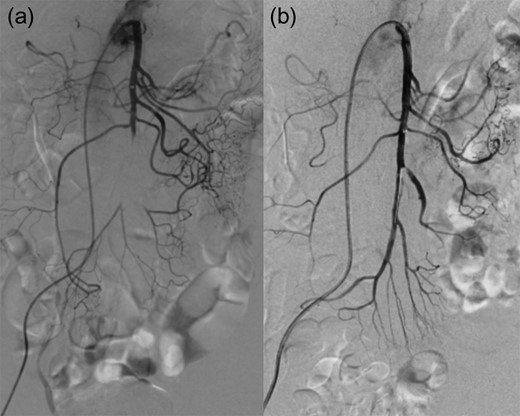

The operation initiated with the patient in the supine position. A 6-French (Fr) guiding sheath was inserted into the right femoral artery. Subsequently, a 4-Fr shepherd hook catheter was placed in the SMA, and then the 0.035-inch guidewire was left in the SMA, and the shepherd hook catheter was changed to a 4-Fr straight catheter. Using this catheter as a foundation, the guiding sheath was placed into the SMA. The contrast injection as well as the CT image showed that the SMA was occluded from the ileocolic artery bifurcation. However, the 0.014-inch guidewire and 4-Fr catheter easily passed the occlusion lesion. Following them, the guiding sheath was placed close to the central side of the occlusion lesion. While moving the catheter, negative pressure was applied from the sheath to perform thrombus aspiration. This procedure was repeated several times, and small white materials and red thrombus were detected in the aspirated blood. After several aspiration, although some thrombus reduction was observed and the flow of the jejunal branch improved, thrombus still remained much and migrated to the central side. Judging that there was a limit to aspiration alone, we placed a 4 mm × 40 mm RIVAL (Bard, Covington, USA) into the occlusion area and PTA was carried out by inflating a balloon slowly. After PTA, the patient’s abdominal pain improved, and the thrombus grew smaller but remained. We injected urokinase solution (60 000 unit) into the artery, leaving the sheath and finishing the operation at once. Next day, further reduction of the thrombus was seen by contrast injection and additional PTA was performed using 4 mm × 40 mm Angiosculpt (PHILIPS, Amsterdam, Netherlands). After PTA, successful revascularization was achieved in almost all branches (Fig. 2). At this point, surgery was completed.

(a) pre IVR contrast injection (b) post IVR contrast injection.